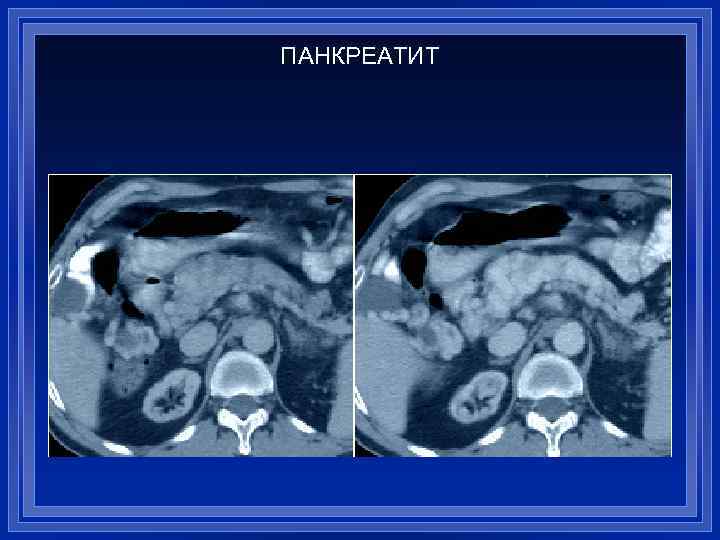

ПАНКРЕАТИТ